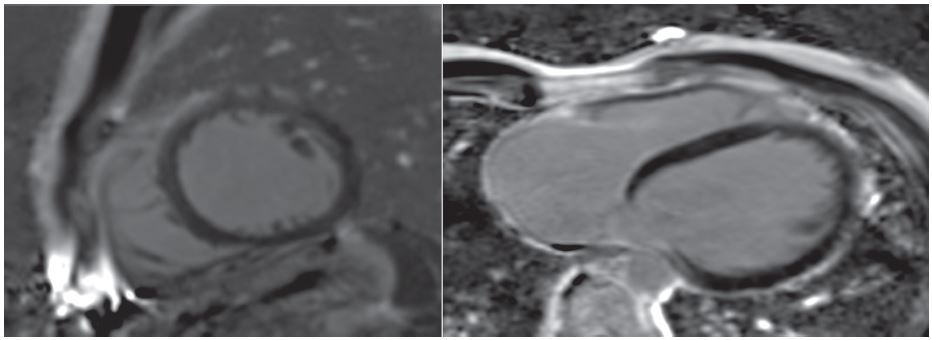

In 2014 he was admitted for additional investigations in a tertial center. A 24 hours Holter ECG monitoring was performed that recorded a ventricular tachycardia with the heart rate of 130-152 b/min, solitary sinus captured beats and a short episode of sinus rhythm (from 4:17 PM till 4:30 PM). The patient was evaluated by TTE with the detection of the decreased LVEF - 25% (Table 1). The coronarography shoved normal coronary arteries. He was also evaluated by cardiac magnetic resonance imaging (MRI) with the detection of a dilative cardiomyopathy pattern, without any changes suggestive for arrhythmogenic right ventricle dysplasia (Figure 2).

Figure 2: Cardiac magnetic resonance imaging. Cardiac magnetic resonance demonstrating an absence of scars with late-gadolinium enhancement.

In a patient with persistent or paroxysmal arrythmia and ventricular dysfunction the AiCMP should be suspected. In our patient there were some clues to the diagnosis of the AiCMP as normal TTE parameters in the onset of the disease and the absence of positive late gadolinium enhancement areas on cardiac MRI.